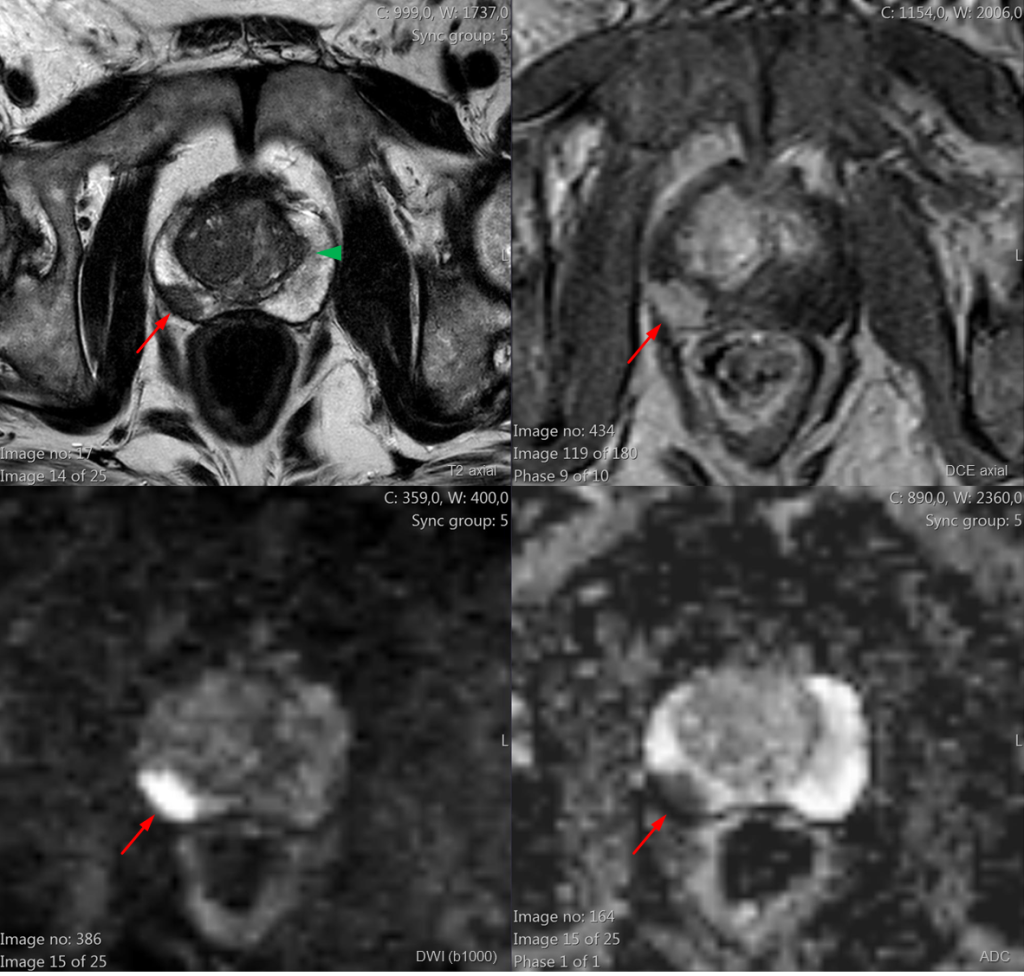

Lesão nodular na zona periférica direita com extensão extracapsular (seta vermelha) – com hipossinal T2 (imagem 1), curva de realce dinâmico positiva (imagem 2) e restrição à difusão (imagens 3 e 4).

PI-RADS 5 – Muito alta probabilidade de neoplasia clinicamente significante.